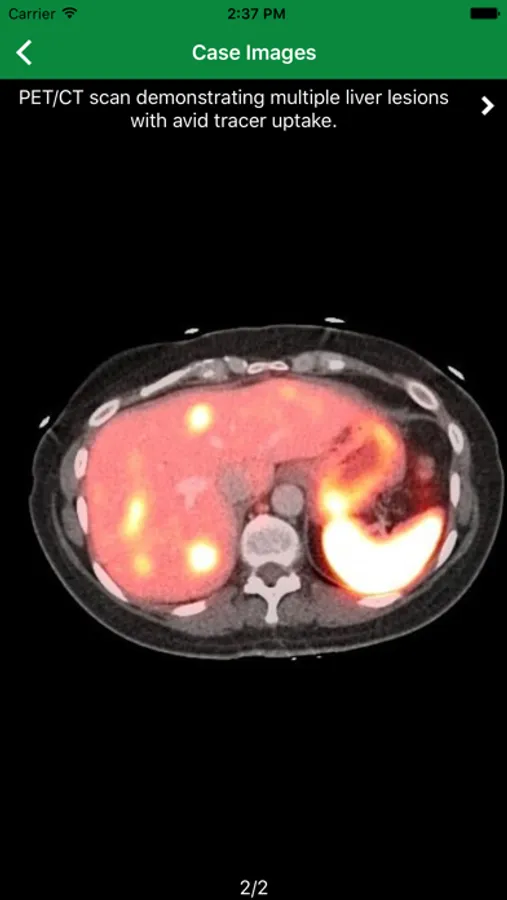

ARRS 2020 Screenshots